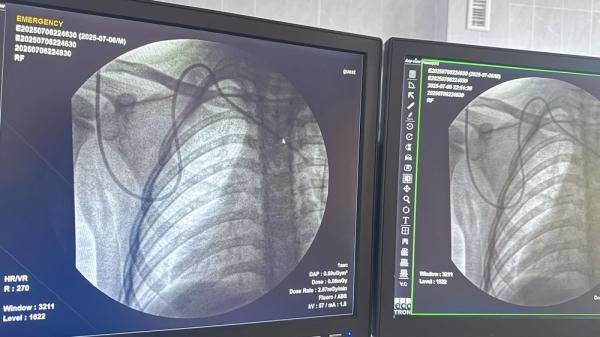

Впервые самостоятельно установили порт-систему ребенку с онкологическим диагнозом, сообщил 7 июля заведующий отделением детской онкологии и онкогематологии НЦОМиД Султан Стамбеков на своей странице в соцсетях.

«Если раньше мы проводили такие процедуры под наблюдением наших уважаемых коллег из России, то теперь мы освоили этот метод и применяем его в Кыргызстане самостоятельно. Совместно с Анваром Мавляновым и Тураббаевым Фаезбеком мы провели эту процедуру. Это не просто медицинская манипуляция — это шаг к более комфортному, безопасному и современному лечению наших маленьких пациентов», — рассказал он.